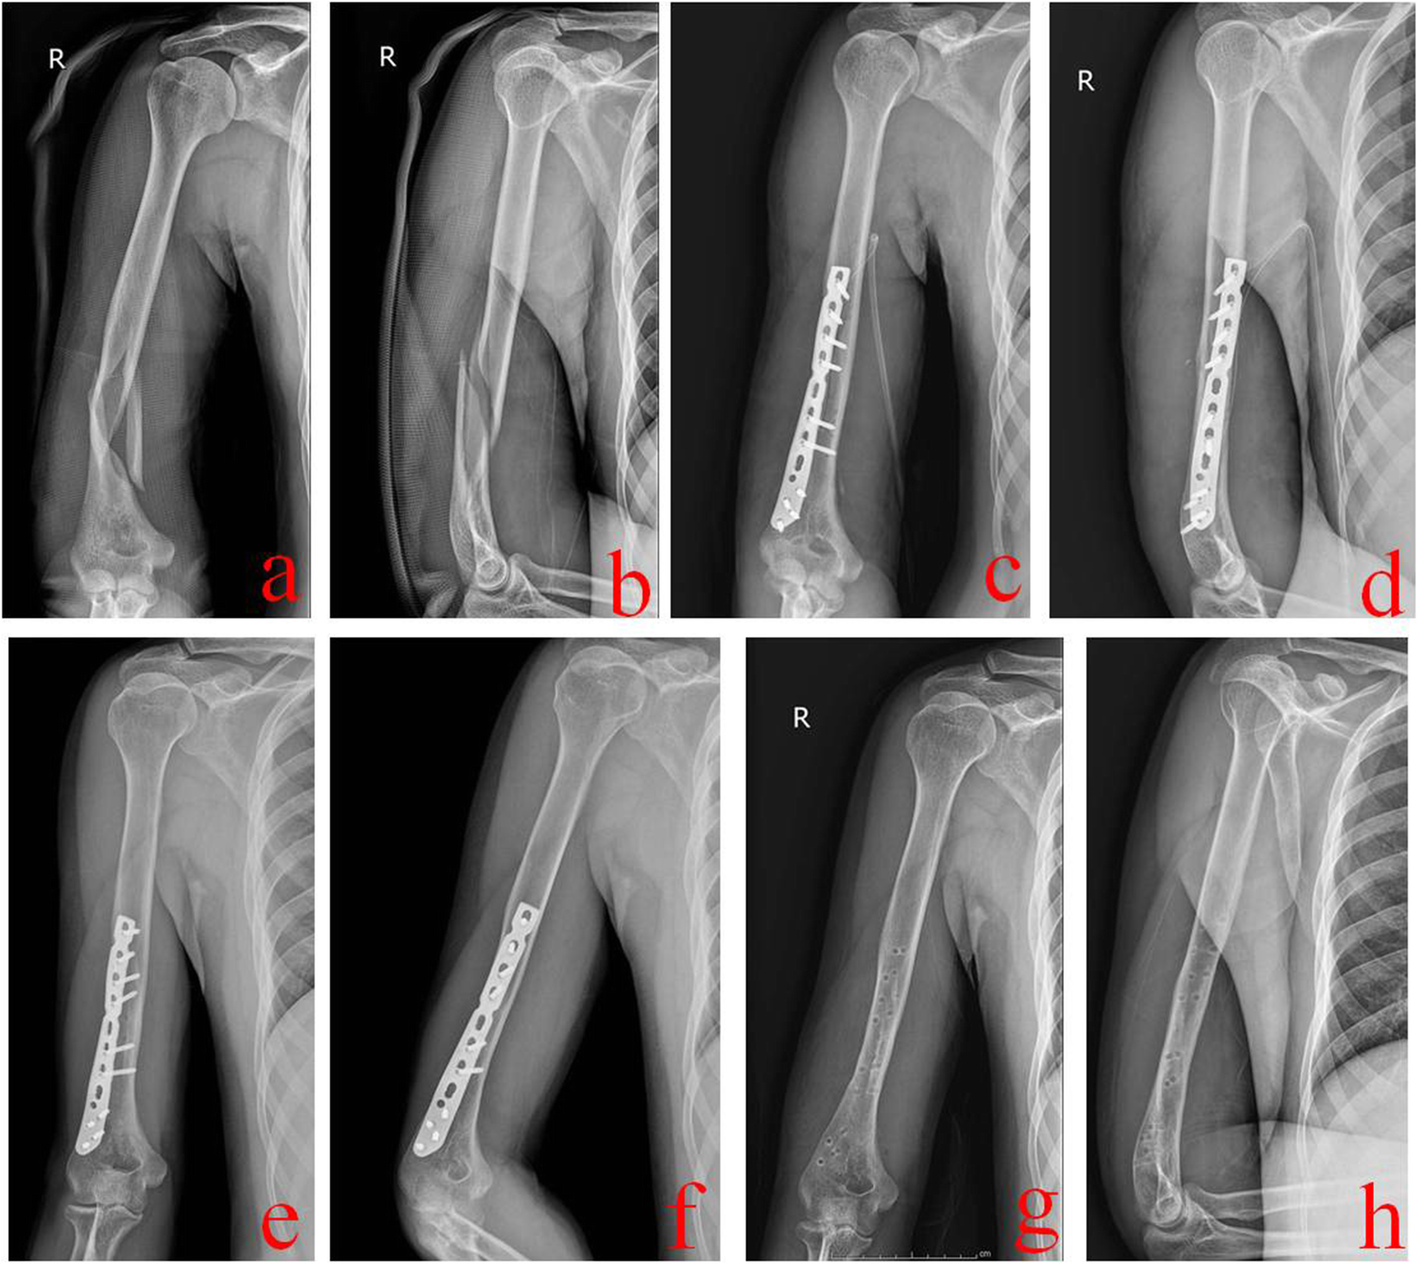

Fig. 3

A 24-year-old male was treated by AATI technique. a and b Preoperative X-ray films showed a middle and distal-third humeral shaft fracture. c and d Immediate postoperative X-ray films showed good reduction and fixation. e and f One year after operation, X-ray films showed that this fracture healed well. g and h X-ray films after removal of the internal fixation plate. AATI stands for the anterolateral approach with two incisions